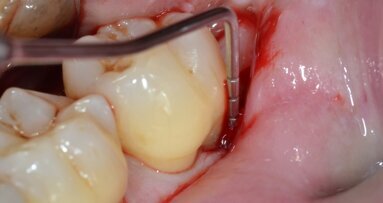

Sono state proposti diversi tipi di terapie in base alla gravità della lesione tra cui: scaling, root planing da solo o in associazione a plastica della forca, tecniche rigenerative con o senza bone graft con aggiunta di membrane per isolare il difetto in modo tale da promuovere la rigenerazione della membrana periodontale22 o, nella peggiore delle situazioni, estrazione dentaria. Se il molare tippato ha un coinvolgimento della forca prima dell’uprighting ortodontico, la simultanea estrusione può peggiorare il difetto, soprattutto se in presenza di un’infiammazione parodontale23,24.

Mayer e Basdra nel loro case report25 suggeriscono un trattamento ortodontico in associazione a terapia chirurgica che consiste in resezione della radice ed allineamento ortodontico delle radici separate.

Nel case report di Ogihara e Marks26 si riporta una terapia ortodontica/rigenerativa combinata del primo molare superiore di destra con difetto della forca. Otto settimane dopo la terapia rigenerativa, hanno iniziato l’estrusione dell’elemento. Alla fine del trattamento, una diagnosi radiografica ha riportato il successo del trattamento.